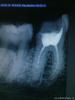

Л Ю С Я Опубликовано 21 марта, 2013 Поделиться Опубликовано 21 марта, 2013 Ааааа и тут анкер Ссылка на комментарий

Ico Опубликовано 21 марта, 2013 Поделиться Опубликовано 21 марта, 2013 Ааааа и тут анкер Ужос!!Под вкв не брали,што оставалось делать?Второи год копит на коронку :lol: 1 Ссылка на комментарий

Ico Опубликовано 21 марта, 2013 Поделиться Опубликовано 21 марта, 2013 Паш, это реколл того дедули? Мой мегареспект!!!16 зуп,пациенту 84 года!! 1 Ссылка на комментарий

Л Ю С Я Опубликовано 21 марта, 2013 Поделиться Опубликовано 21 марта, 2013 16 зуп,пациенту 84 года!!Зубастый однако дедуля Ссылка на комментарий

Ico Опубликовано 21 марта, 2013 Поделиться Опубликовано 21 марта, 2013 Зубастый однако дедуляФизик - ядерщик. Ссылка на комментарий